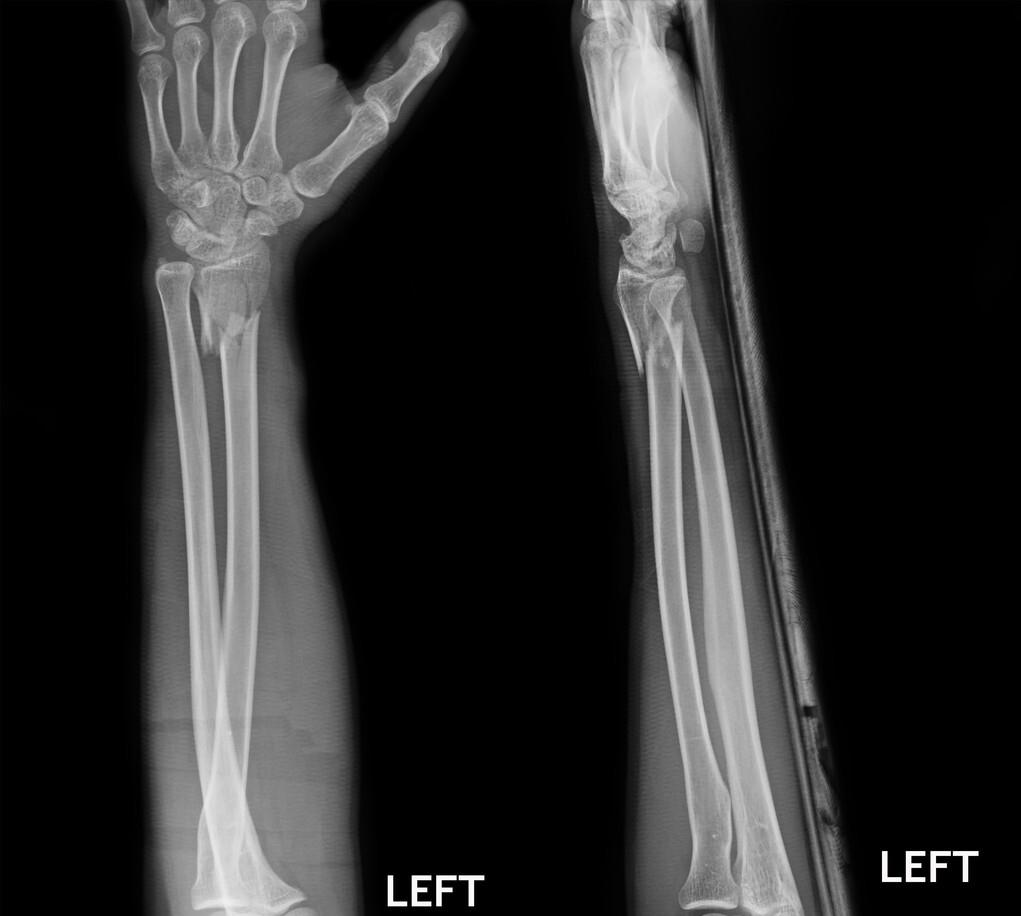

三十多岁的一个女性,前臂桡骨靠近手腕的部位骨折了。

赶快到医院看吧,片子一拍,桡骨远端骨折。